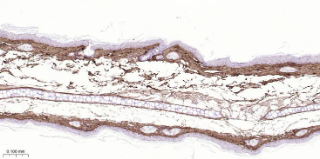

Immunohistochemical analysis of paraffin embedded Mouse skin tissue slide using IHC0648M (Mouse Collagen I Kit).